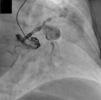

Transthoracic echocardiography performed at the patient's bedside showed moderate depression of left ventricular systolic function (40% ejection fraction) and severe mitral regurgitation. Since abdominal aortic aneurysms are frequently associated with clinically significant coexisting coronary artery disease, after hemodynamic stabilization coronary angiography was performed. This showed multiple aneurysms involving all the main coronary arteries without significant stenosis (Figure 1). To better assess the coronary arteries cardiac computed tomography was performed, which showed a large aneurysm involving the anterior descending and circumflex arteries. The right coronary artery also had an aneurysm, smaller than in the left coronary (Figures 2 and 3).